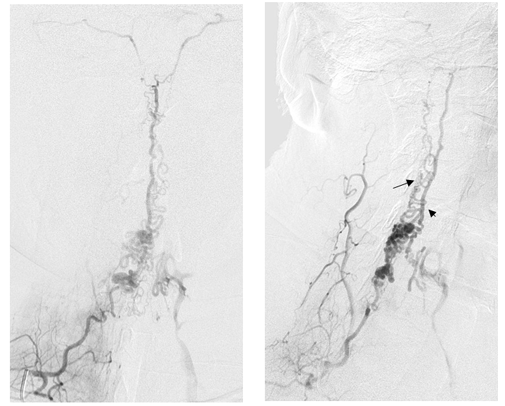

正侧位,甲状颈干造影静脉期,显示瘘口主要经颈髓前(箭头)、后静脉(黑箭)引流入颅,引流静脉迂曲、增粗、扩张,部分经椎旁静脉丛引流。动静脉之间未见明显畸形团结构。

左侧甲状颈干选择性造影,显示瘘口位置及扩张静脉与对侧形态形态相似。考虑双侧颈升动脉供应相同瘘口。予以ONXY进行栓塞瘘口,栓塞物控制于扩张的静脉球内。